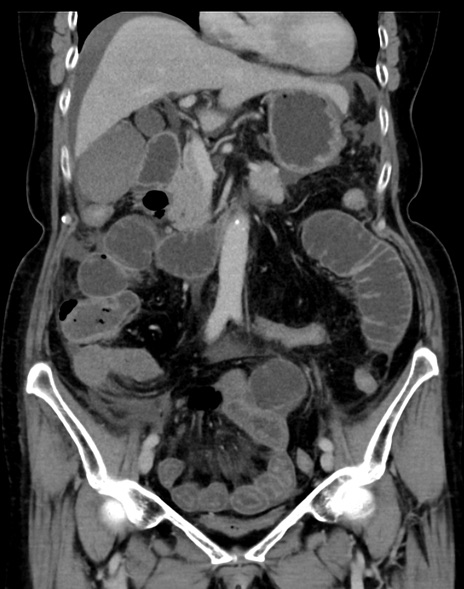

症例13 CT(冠状断像)1日半後